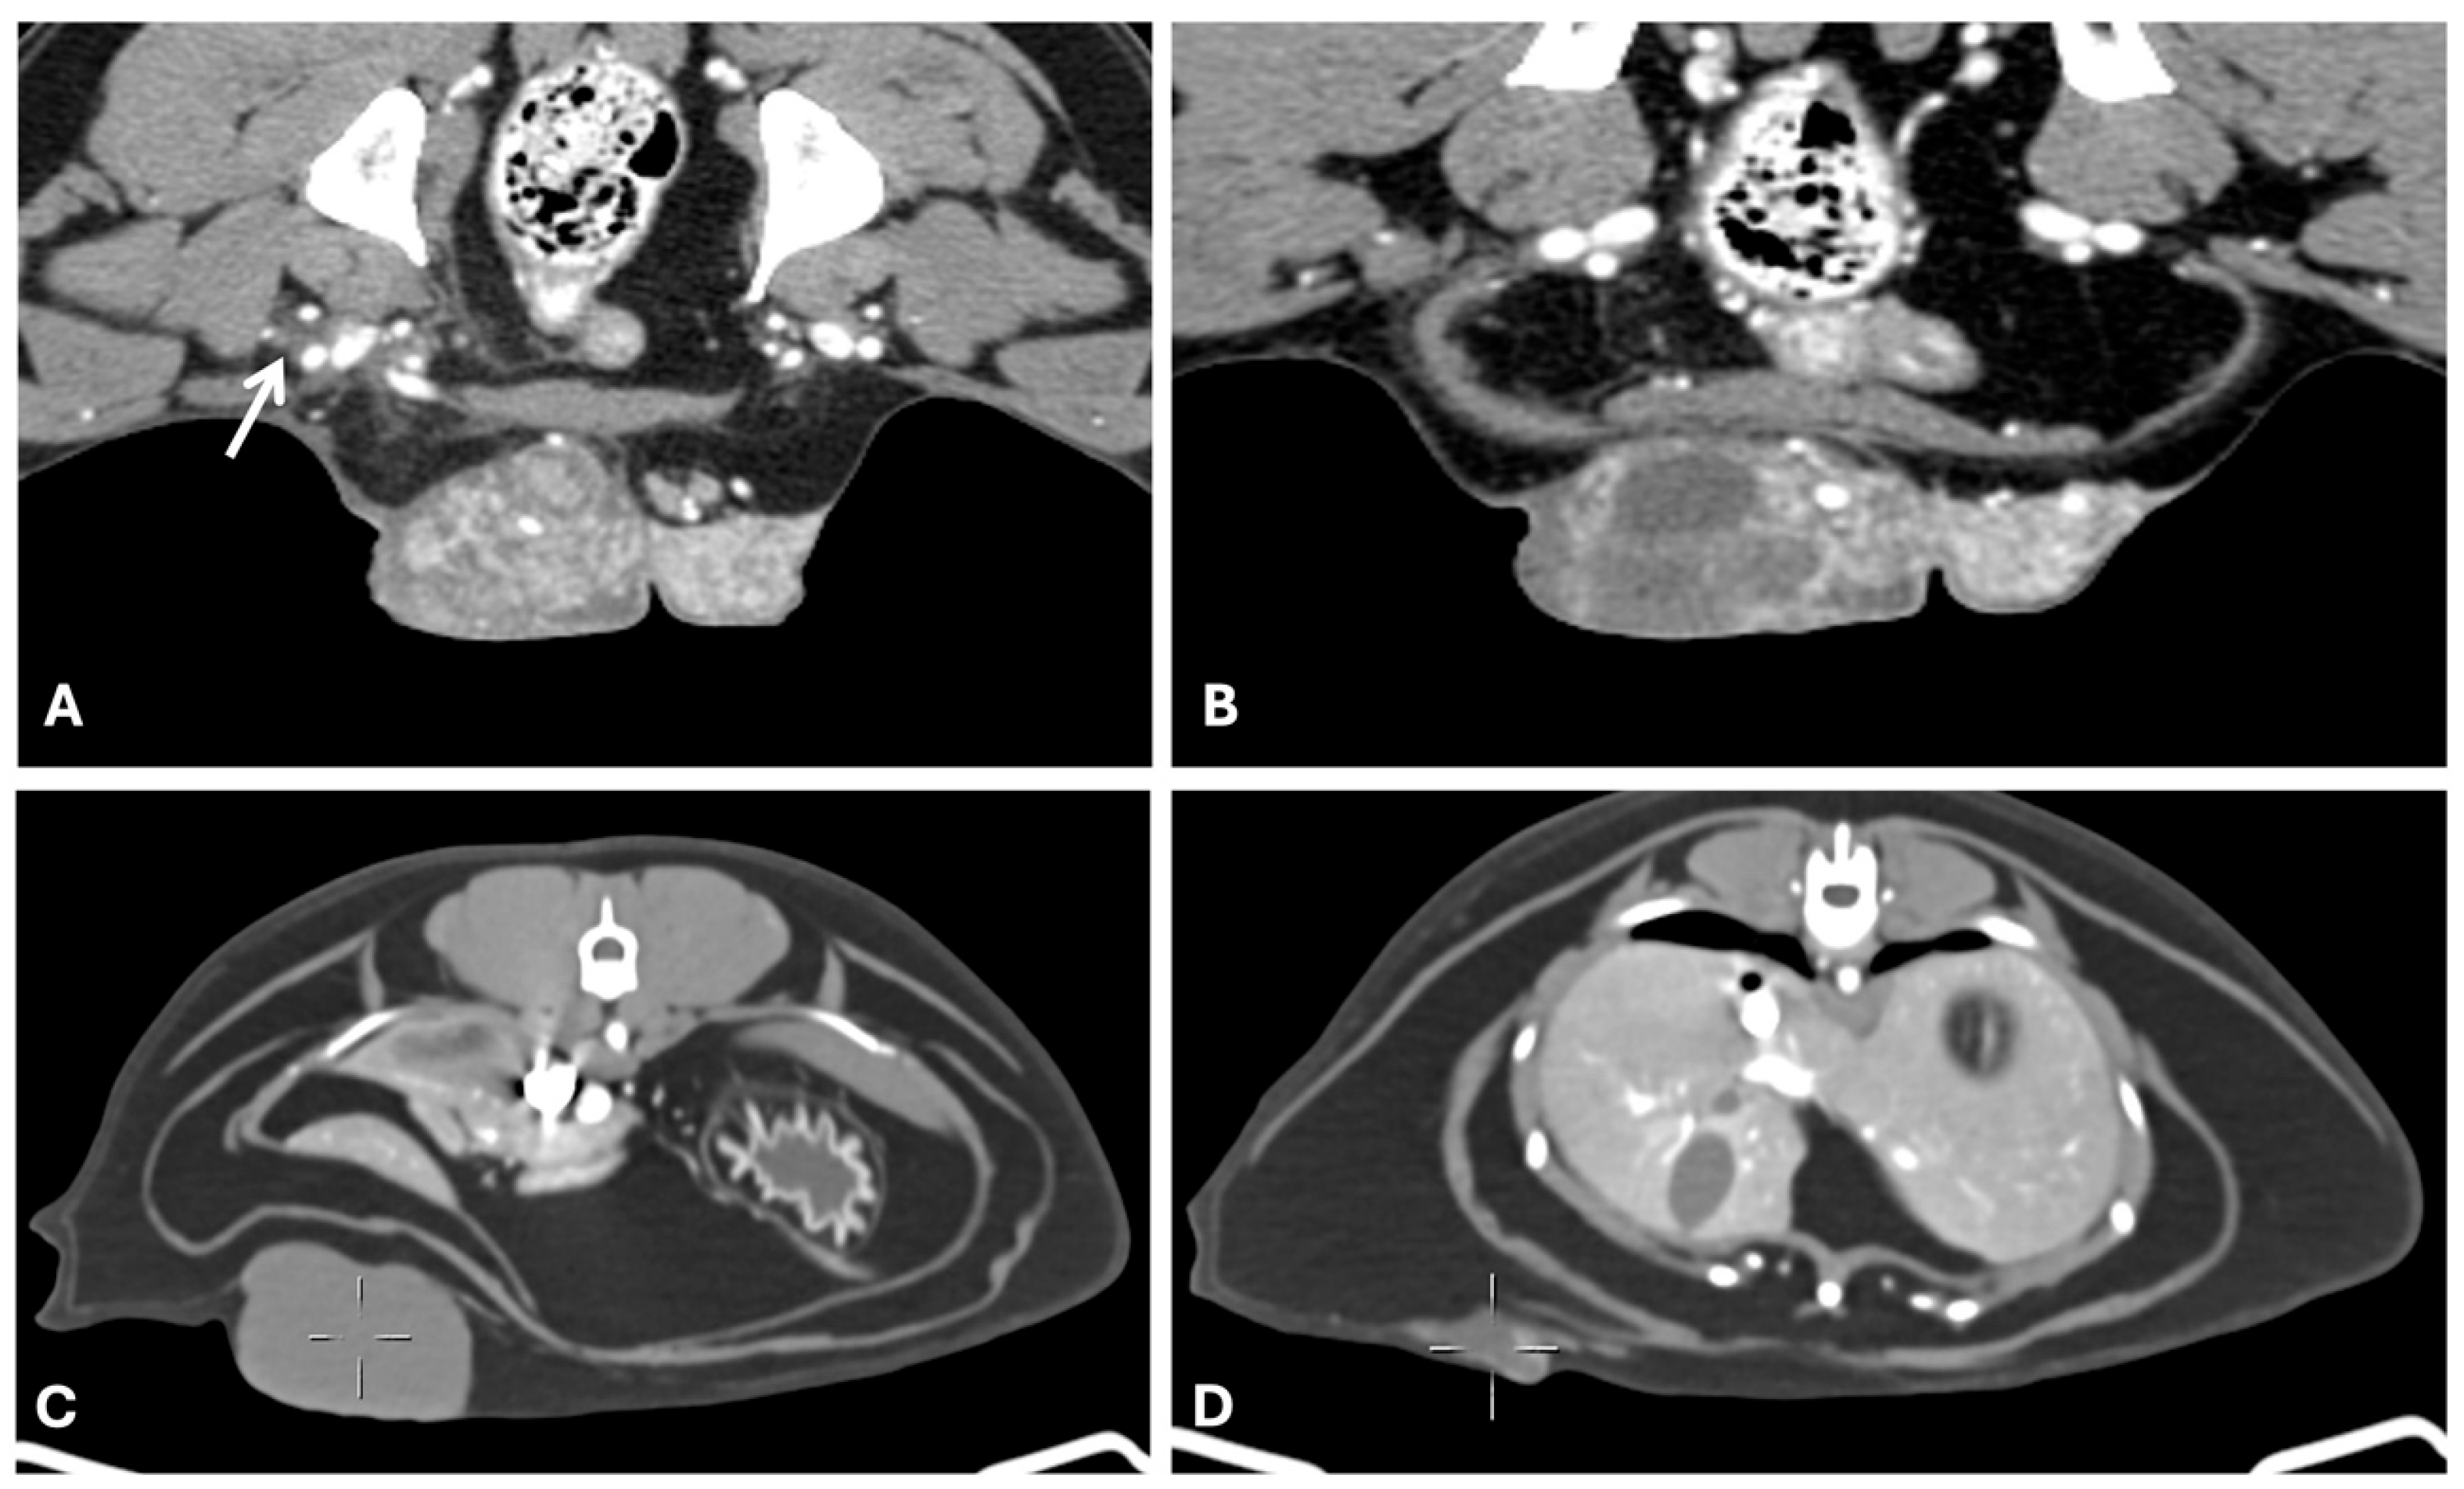

3.2. Computed Tomography

- Soultani, C.; Patsikas, M.N.; Mayer, M.; Kazakos, G.M.; Theodoridis, T.D.; Vignoli, M.; Ilia, T.S.M.; Karagiannopoulou, M.; Ilia, G.M.; Tragoulia, I.; et al. Contrast Enhanced Computed Tomography Assessment of Superficial Inguinal Lymph Node Metastasis in Canine Mammary Gland Tumors. Vet. Radiol. Ultrasound 2021, 62, 557–567. [Google Scholar] [CrossRef]

- Soultani, C.; Patsikas, M.N.; Karayannopoulou, M.; Jakovljevic, S.; Chryssogonidis, I.; Papazoglou, L.; Papaioannou, N.; Papadopoulou, P.; Pavlidou, K.; Ilia, G.M.; et al. Assessment of Sentinel Lymph Node Metastasis in Canine Mammary Gland Tumors Using Computed Tomographic Indirect Lymphography. Vet. Radiol. Ultrasound 2017, 58, 186–196. [Google Scholar] [CrossRef] [PubMed]

- Otoni, C.C.; Rahal, S.C.; Vulcano, L.C.; Ribeiro, S.M.; Hette, K.; Giordano, T.; Doiche, D.P.; Amorim, R.L. Survey Radiography and Computerized Tomography Imaging of the Thorax in Female Dogs with Mammary Tumors. Acta Vet. Scand. 2010, 52, 20. [Google Scholar] [CrossRef]

- Fonseca Pinto, A.C.B.C.; Iwasaki, M.; Figueiredo, C.M.; Cortopassi, S.R.G.; Sterman, F.d.A. Tomografia Computadorizada do Tórax de Cadelas Portadoras de Neoplasias Malignas. II—Avaliação dos Campos Pulmonares. Braz. J. Vet. Res. Anim. Sci. 2007, 44, 174–182. [Google Scholar] [CrossRef]

| CT | Removal of superimposition of structures, high sensitivity, contrast resolution and spatial resolution [34] | Low soft tissue contrast, cost, low availability, need for anesthesia [34] | Yes [72] | 2nd line (pulmonary, lymphatic and abdominal metastases) [31,73] |